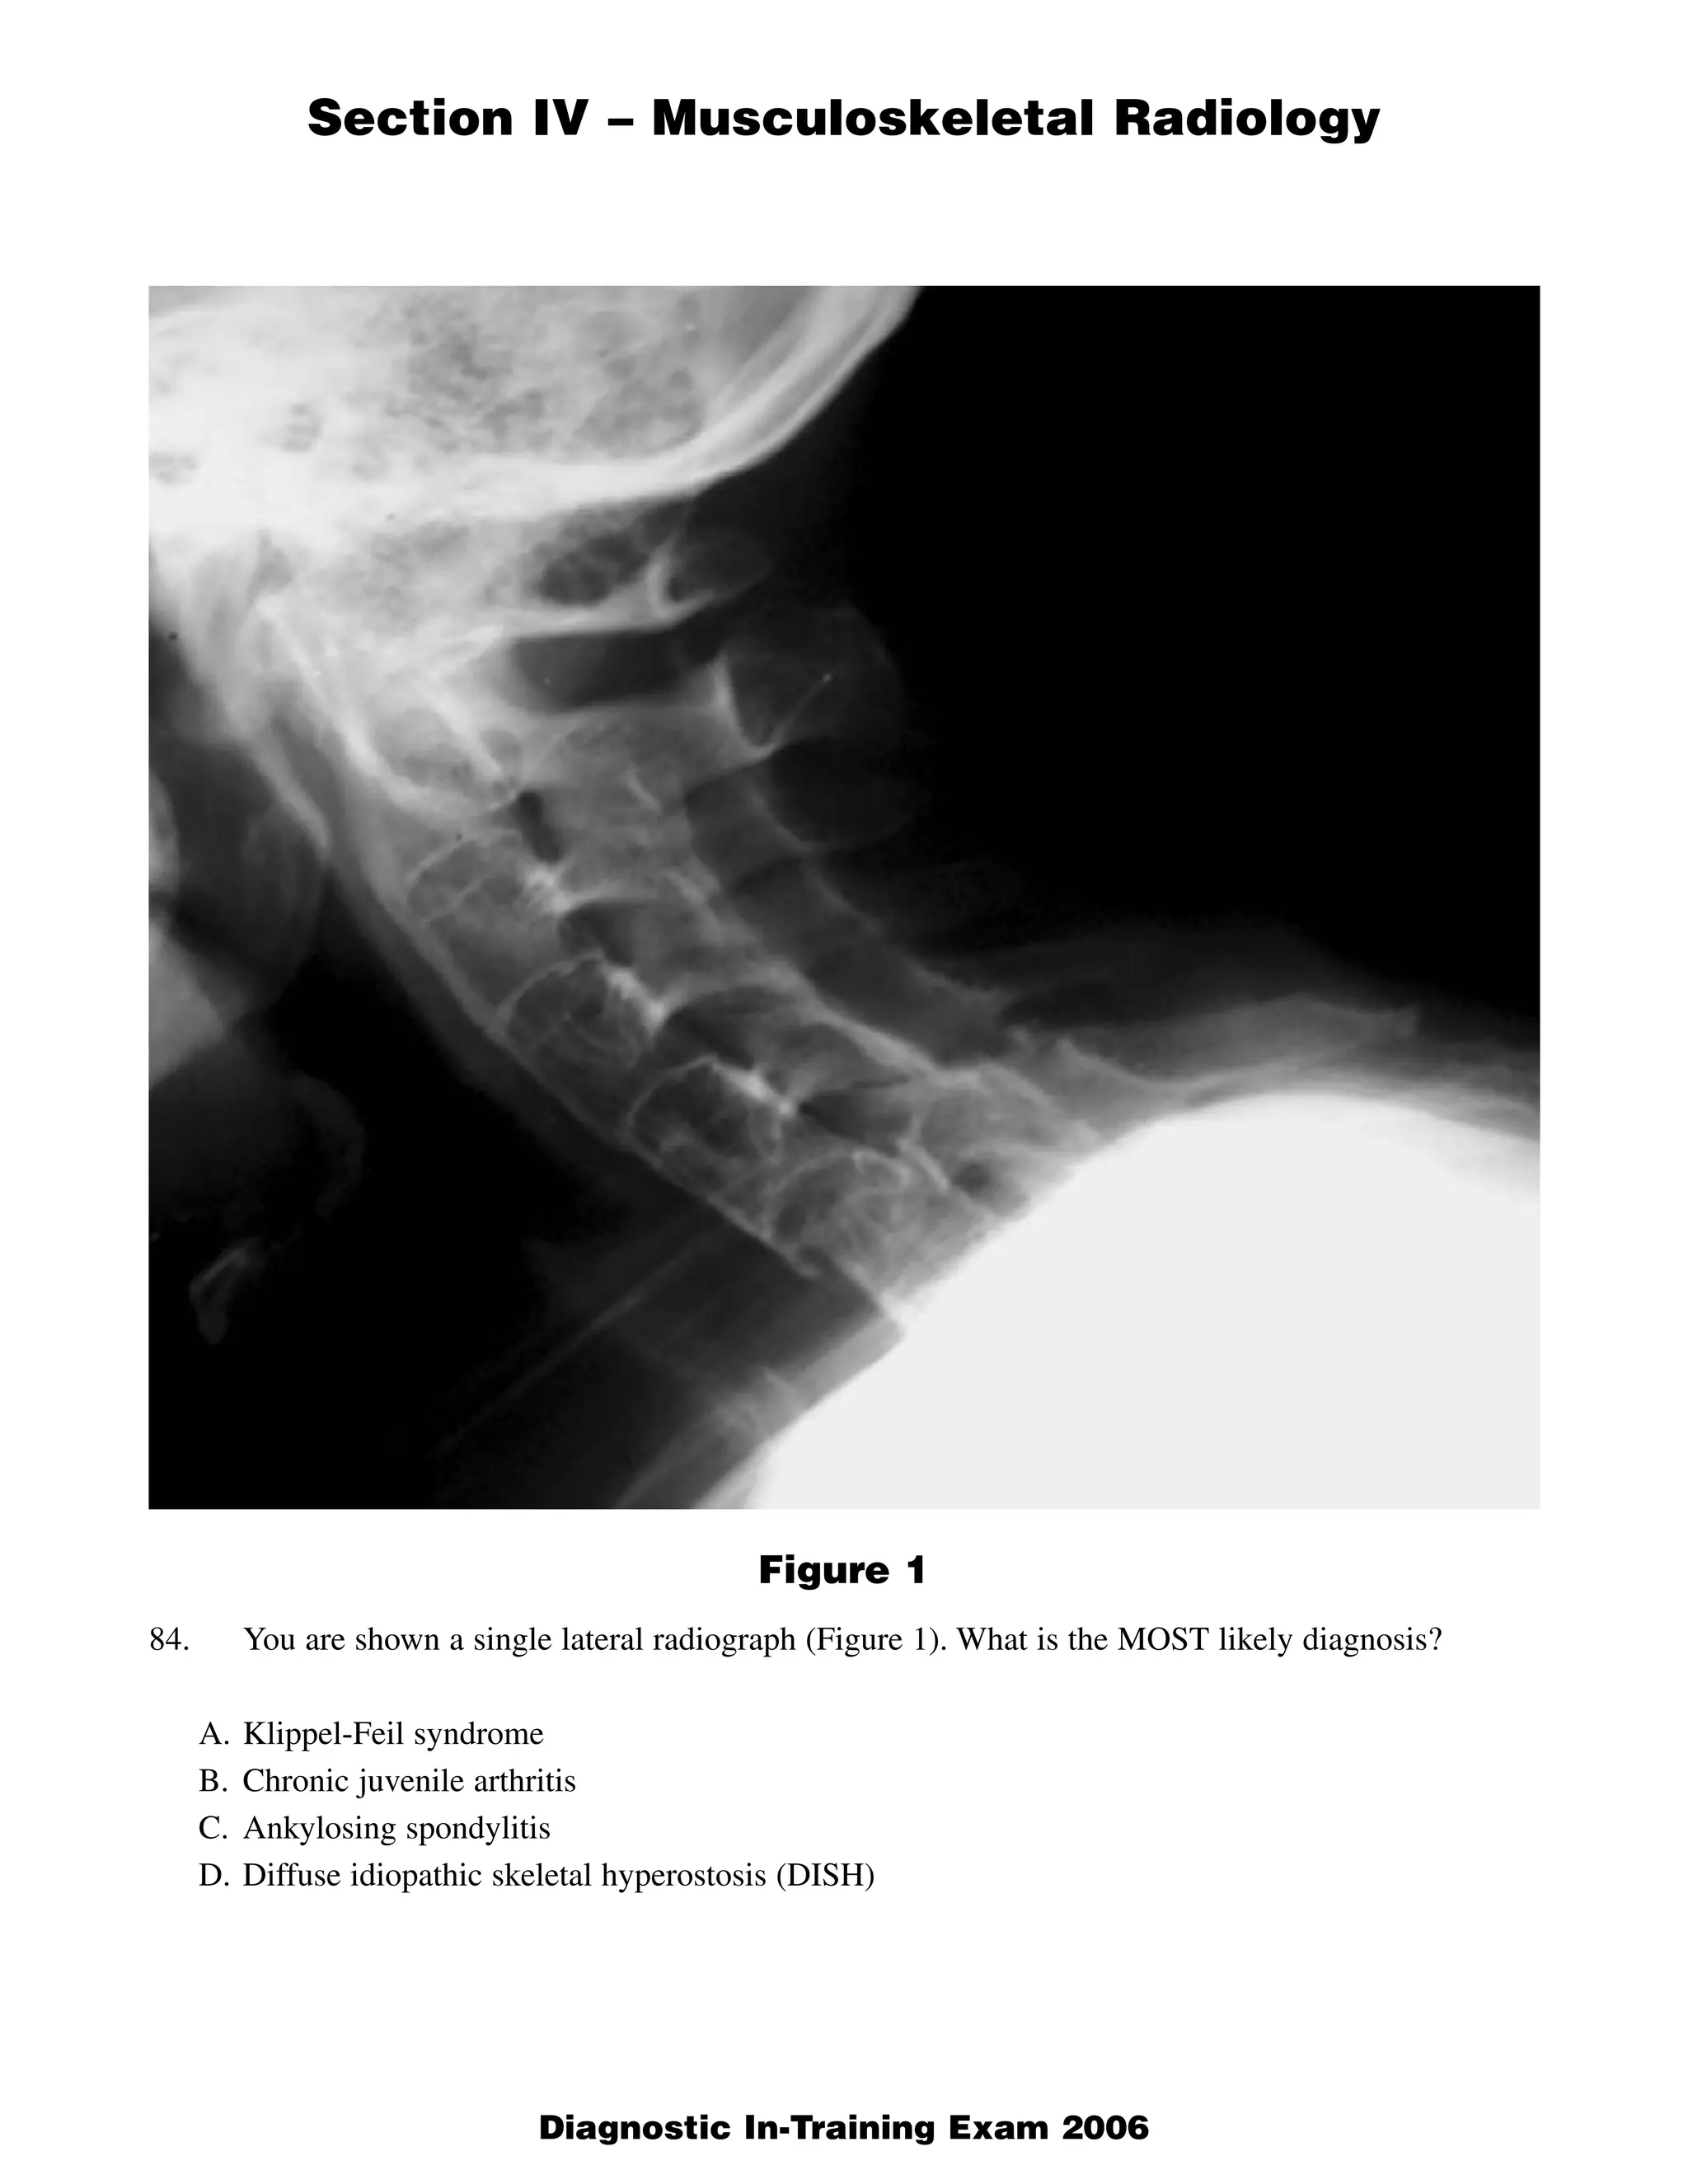

This document contains a radiology case study with 4 images (Figures 1-4) and accompanying questions. Figure 1 shows a lateral cervical spine x-ray. The diagnosis is ankylosing spondylitis based on diffuse bony ankylosis throughout the cervical spine. Figure 2 shows MRI images of the knee with a diagnosis of discoid meniscus due to excessive meniscal tissue. Figure 3 shows x-rays of the leg with a diagnosis of Brodie's abscess, seen as an elongated lytic lesion in the tibia. Figure 4 shows knee images of a 13-year-old boy with a diagnosis of chondroblastoma, seen as a well-defined lesion in the proximal tib